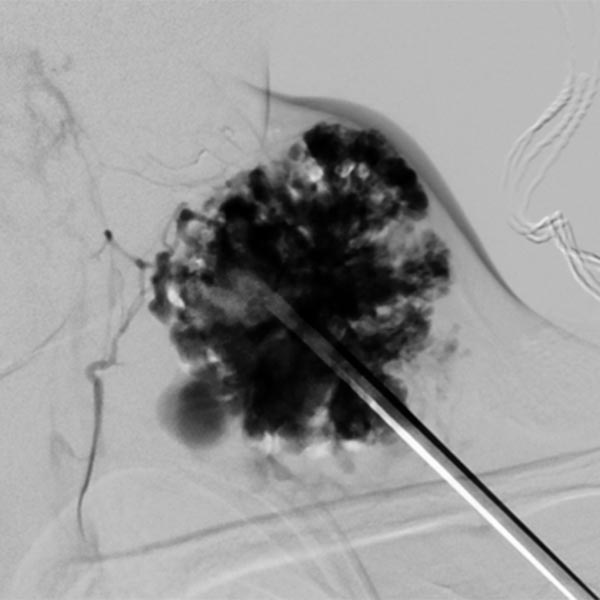

Sclerotherapy was performed in view of the rapid growth in size and recurrent painful thrombophlebitis. The contrast injection via an inserted puncture needle depicted here shows extensive contrasting of the venous malformation, thus good conditions for successful sclerotherapy.

Digital subtraction angiography after contrast injection via the same needle also shows very clearly the almost complete filling of the venous malformation from this needle position. Only small, very thin-lumen communicating veins present themselves. Therefore, a large part of the venous malformation can be sclerosed from this needle position.